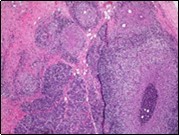

Figure 1.Granulomatous mastitis with the configuration of epitheloid cell granuloma and a lymphoid and plasma cell infiltrate9.

Granulomatous  mastitis with the configuration of epitheloid cell granuloma and a lymphoid and plasma cell infiltrate9.

Core needle biopsy of idiopathic granulomatous mastitis enunciates multiple aggregates of non- caseating epitheloid cell granulomas within and encompassing breast lobules, constituted of epitheloid histiocytes, lymphocytes, neutrophils and multinucleated giant cells. Granulomatous inflammation is predominantly lobulo-centric. The inflammation is preponderantly composed of lymphocytes, plasma cells, epitheloid histiocytes, multinucleated giant cells and neutrophils. Neutrophils can configure micro-abscesses and encompass vacant micro-cystic cavities, morphological features which are in common with cystic neutrophilic granulomatous mastitis. Non specific lobulitis along with a lymphoid and plasma cell infiltrate accompanies the granulomatous inflammation. Necrosis is usually absent. Neutrophilic micro-abscesses can be accompanied by fistula formation 4, 5.

Multinucleated giant cells are detected in an estimated three fourths (78.5%) instances. Plasma cells are discernible in around half (53.9%) of the subjects and usually appear at the margins of cystic vacuoles with centric accumulation of neutrophils within the granulomas.